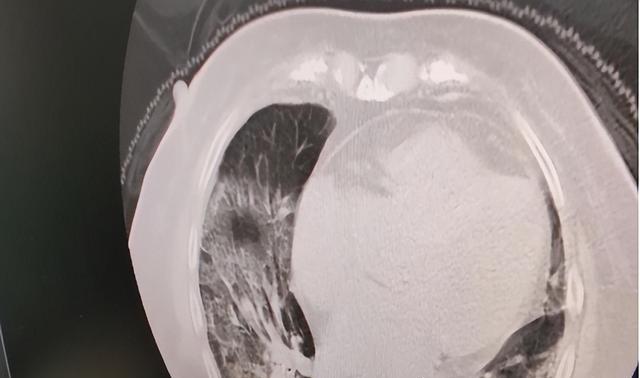

媒体和许多网友爆出了“白肺”这一病症 , 某些高龄老人在感染奥密克戎以后 , 出现了呼吸困难甚至是晕厥的情况 , 送到医院通过X光或者CT影像检查以后发现肺部大部分都白了 。 这种临床症状非常危险 , 专家称重症“白肺”的死亡率在40%以上 。

之所以会出现白肺主要是肺泡出现了较为严重的“炎症”并且存在渗出的情况 。 根据专业人士介绍 , “白肺”的明显特征是在医学仪器检查下 , 肺部白化的面积达70%-80% , 网络上很多人公布的情况实际上不是白肺 。